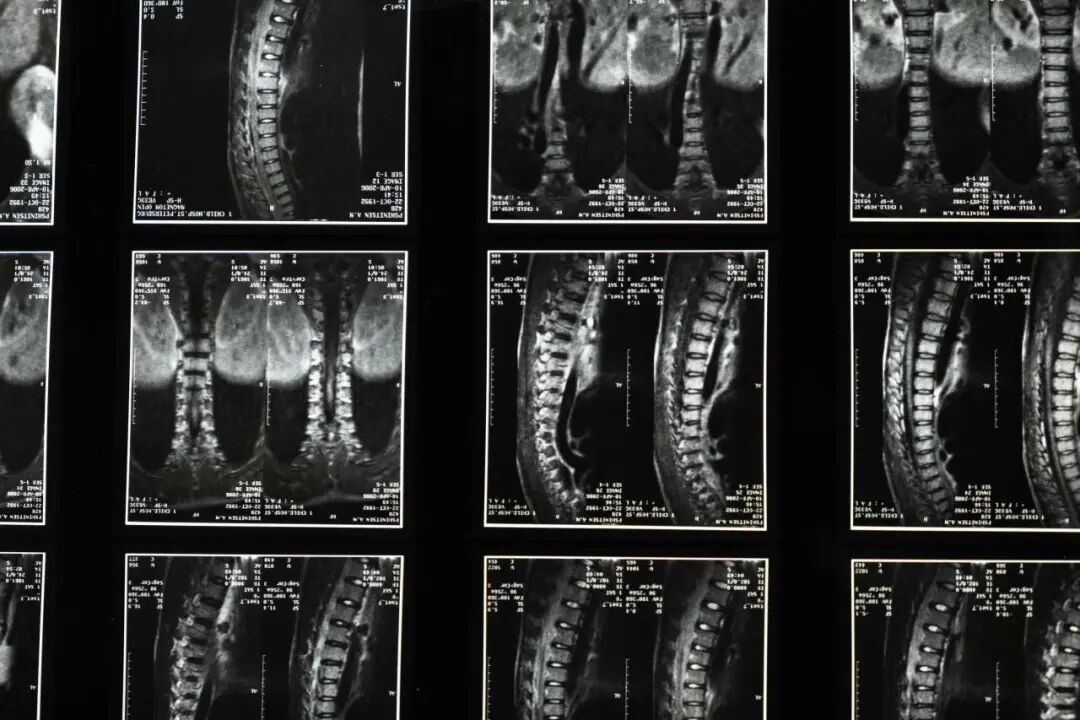

检查报告“腰椎间盘膨出”,腰不行了吗?

随着影像学检查的普及,“腰椎间盘膨出”这个诊断越来越频繁地出现在体检报告和门诊病历中。很多人看到这个结果,第一反应往往是焦虑和担忧:是不是腰不行了?事实上,腰椎间盘膨出远没有想象中那么可怕。下面为你全面解读这一常见的影像学发现。

腰椎间盘由两部分组成:中央是富有弹性的胶状物质(髓核),外围是坚韧的纤维环。随着年龄增长、日常劳损或不当用力,纤维环可能逐渐变得松弛、弹性下降,导致整个间盘向周围均匀、对称地轻微膨出,就像轮胎轻微鼓包一样,但纤维环并没有破裂,这就是影像报告上所说的“膨出”。

大量研究显示,在没有任何腰痛的成年人中,进行腰椎MRI检查,约有30%~40%的人会显示出不同程度的间盘膨出或突出。这意味着,影像学上的发现不一定等同于疾病,也可能是一种与年龄相关的退行性改变。

现代医学影像技术(尤其是MRI)极为敏感,能够显示极其细微的结构变化。然而,影像学发现必须与临床症状相结合才有意义,常见的情况有:有些人影像显示明显的椎间盘膨出,却没有任何症状;有些人腰痛剧烈,影像却只有轻微的改变。疼痛程度与影像严重程度并不总是成正比。